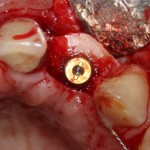

Для решения поставленной клинической задачи мы выбрали имплантационную систему Xive. Из имеющихся у нас трёх имплантационных систем, она лучше всего подходит для немедленной имплантации и немедленной нагрузки, и вот, почему:

Теоретически, для данной работы мы можем использовать абсолютно любую имплантационную систему, но с Xive это сделать проще. Тем более, что в клинике мы держим склад из более, чем трехсот имплантатов и компонентов, поэтому не переживаем по поводу того, что к моменту операции чего-то не будет в наличии. У нас всё всегда есть.

В процессе ирригации лунки промываются, что позволило нам еще раз подтвердить ранее сделанные выводы. С помощью аналогов имплантатов, входящих в хирургический набор Xive, мы проверили возможность стабилизации имплантатов в будущих лунках. Исходя из правил подбора и позиционирования имплантатов (я очень рекомендую почитать об этом здесь>>) мы остановились на Xive S диаметром 3,4 мм и длиной 13 мм.

По ряду уже упомянутых выше причин, для решения этой клинической задачи мы выбрали имплантаты Xive. Лунки для них мы уже приготовили. возможную первичную стабильность оценили. Имплантаты мы установили с усилием чуть больше 15-20 Нсм — такого крутящего момента более, чем достаточно, особенно если учесть, что временные коронки будут соединяться между собой.